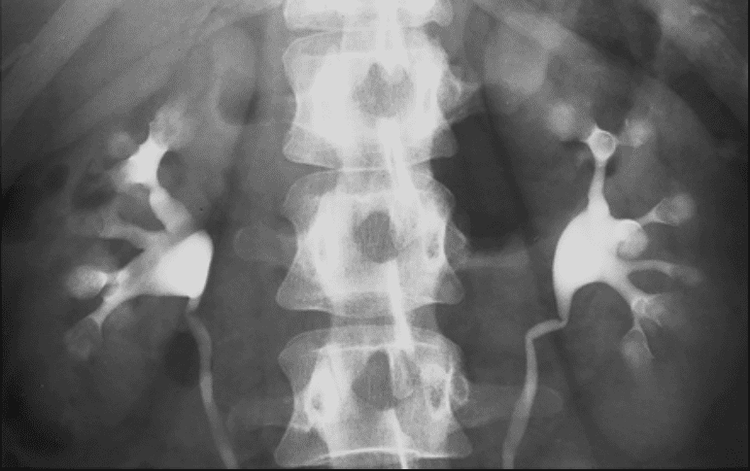

Chụp Xquang hệ tiết niệu có bơm thuốc cản quang tĩnh mạch là kỹ thuật chẩn đoán hình ảnh chụp x-quang hệ tiết niệu có kết hợp tiêm chất cản quang vào tĩnh mạch để giúp bác sĩ đánh giá thận, niệu quản và bàng quang của người bệnh.

Chụp thận thuốc tĩnh mạch là kỹ thuật sử dụng tia X kết hợp với thuốc cản quang để bác sĩ có thể nhìn hình ảnh giải phẫu của thận, bàng quang và niệu quản. Kỹ thuật này không được sử dụng thường xuyên, thay vào đó, các bác sĩ sẽ sử dụng các kỹ thuật chẩn đoán hình ảnh khác ít tác dụng phụ hơn như chụp CT.

• Tiến hành chụp X quang theo các mốc thời gian gồm (1) thuốc cản quang đi tới thận rồi đi tới (2) niệu quản và (3) đổ vào bàng quang.

Kết quả chụp thận có sử dụng thuốc cản quang